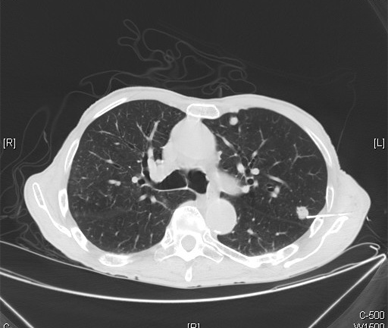

Metastatic prostate adenocarcinoma shown on CT; source: Yale Rosen, Wikimedia Commons